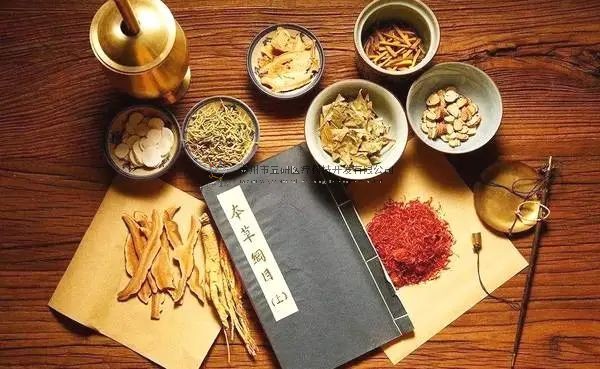

中醫藥是我國重要的衛生、經濟、科技、文化和生態資源,傳承創新發展中醫藥是新時代中國特色社會主義事業的重要內容,是中華民族偉大復興的大事。

中醫藥植根于華夏歷史,源遠流長。如何破除制約中醫藥發展的障礙,促進中西醫結合,更好地服務于患者,是一項亟待解決的事項。

中國接骨學(CO接骨術)(ChineseOsteosynthesis ,CO)中西醫結合治療骨折稱之中國接骨學是中醫骨傷科骨折治療技術的核心技術成果。

這也是從傳統中醫正骨的活血化瘀,去瘀生新,動靜結合,筋骨并重;骨肉相連,筋可束骨,祛腐生肌,煨膿長肉等思想逐漸發展起來的。